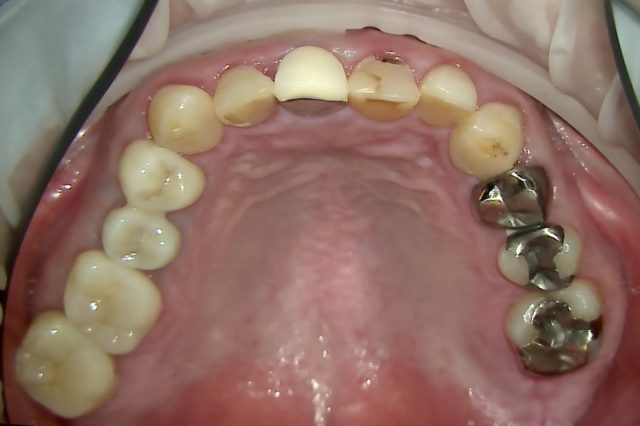

口腔内全体の治療

| 症状 | 口腔内全体の治療を希望されて来院 |

|---|---|

| 治療法 | 両側下顎4.5.6インプラント 天然歯17本補綴 矯正治療 |

| 費用 | 合計約600万円 |

| 通院回数 | 期間約1年半、通院30回程度 |

| 備考 | 全体で問題が起こり機能が失われた状態をトータルでマネジメントし元あった理想に近い形に戻すことを行なっているが、これにはかなりの時間と費用がかかり、大変な治療に耐えていただく必要がある。 また全ては修復物や補綴物やインプラントで見た目と噛む機能を整えているに過ぎず、実際には歯が再生したわけではない。強度の落ちている歯をよく噛める形に整えるという事は、歯が壊れる可能性も同時に上げることになる。つまり施した治療が必ずしも一生保つという事ではない。 よって可能な限りこの状態を長く保つことが出来るよう、治療後は定期的なメンテナンスと、ナイトガード(寝ている間の歯軋りや食いしばりなどの自身でコントロールできない過剰な力から歯を守るマウスピース)の装着が必須となる。 |